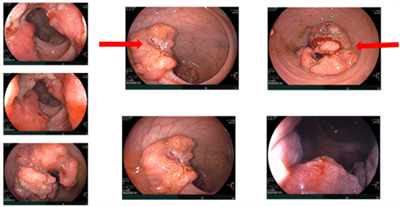

Ca lâm sàng: Điều trị tân bổ trợ ung thư trực tràng giúp giảm giai đoạn và phẫu thuật triệt căn tại Trung tâm Y học hạt nhân và Ung bướu - Bệnh viện Bạch Mai

Ca lâm sàng: Điều trị tân bổ trợ ung thư trực tràng giúp giảm giai đoạn và phẫu thuật triệt căn tại Trung tâm Y học hạt nhân và Ung bướu - Bệnh viện...

Ngày đăng: 23/01/2026

Ung thư trực tràng là một trong những ung thư tiêu hóa thường gặp, với chiến lược điều trị dựa trên giai đoạn bệnh, vị trí u (tính từ rìa hậu môn), nguy cơ xâm lấn mạc treo trực tràng và tình trạng...